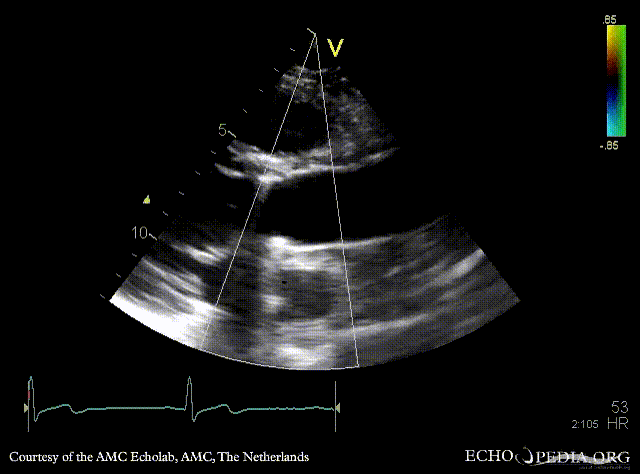

Bentall and aortic valve prosthesis

Courtesy of: AMC Echolab, AMC, The Netherlands

PSAX: aortic valve prosthesis and Bentall in situ PSAX with Color Doppler